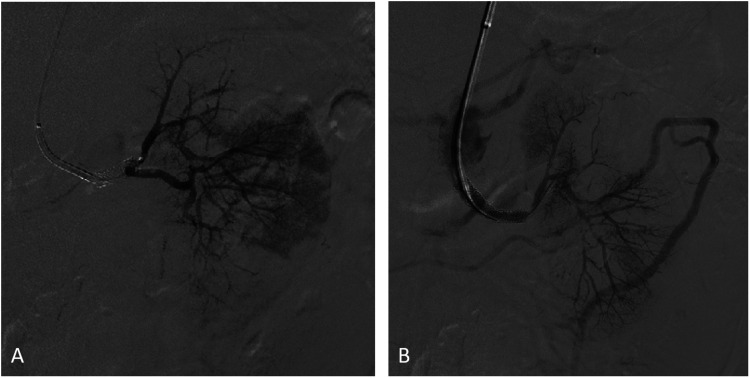

Case report: A 58-year-old male with a history of left renal artery stenosis and stent graft placement presented with symptoms of chest pain, shortness of breath, and flank pain. The patient was admitted to the Intensive Care Unit with the diagnosis of multiorgan failure and subsequent anuria that led to the initiation of hemodialysis. Computed tomography angiography demonstrated an aortic occlusion along with bilateral proximal renal artery occlusion with reconstitution of the mid to distal renal arteries via collateralization. The patient underwent angioplasty with bilateral renal artery stent-graft placement and successful revascularization of proximal renal arteries. Post-operatively, his renal function and urine output improved, and the patient was able to be weaned off hemodialysis along with the benefit of concurrent amelioration of his renovascular hypertension.